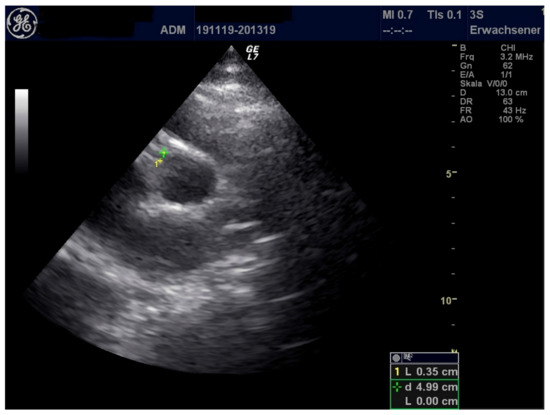

| LCA (mm) | 3.8 | 3.3 | 3.1 |

| RCA (mm) | 3.2 | 4.0 | 2.8 |

| Pericardial effusion (mm) | 7 | 3 | 5 |

| Pleural effusion (mm) | 9 (left), right 0 | 0 | 0 |

| Pericardial effusion (mm) | 0 | 3–7 | <3 |

| Pleural effusion (mm) | 0 (both sides) | 0 | 0 |